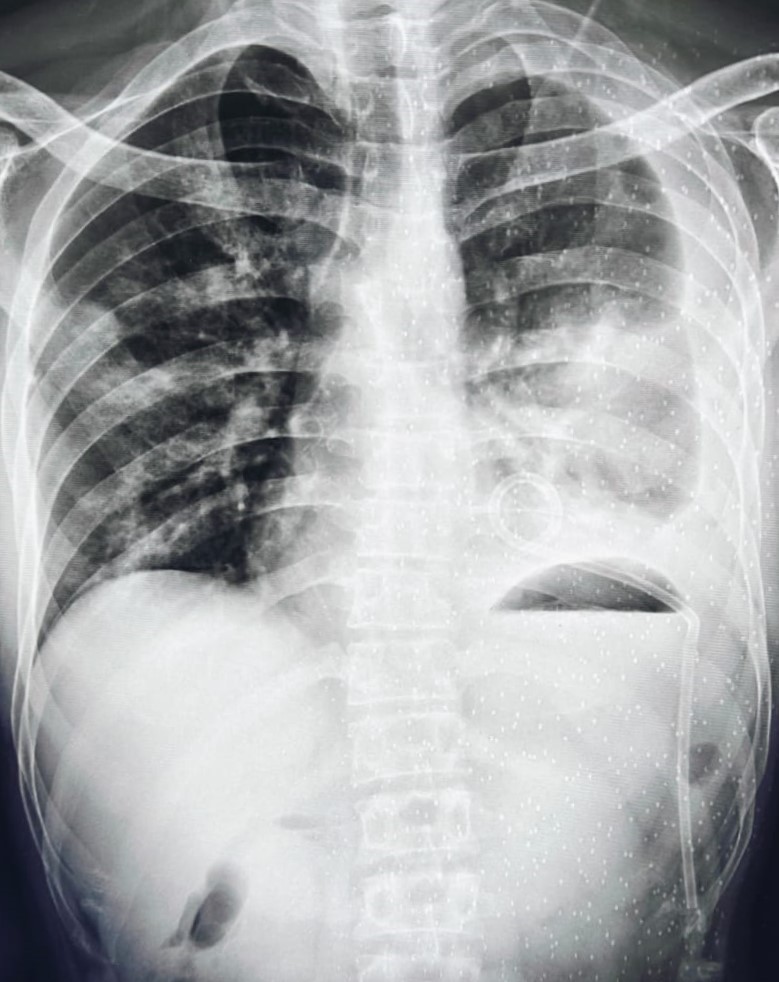

| 338 | IGGMC, Nagpur, Nagpur | P2 | 29-4134 | Rupesh Dongse | Consent taken on Paper | 43 Yrs. |

Provisional Diag : Consolidation

Final Diag : Bilateral Consolidation Community Acquired Pneumonia With Type 1 Respi Failure In Cronic Alcoholic |

Non-TB Case (Confirmed) | Bilateral Consolidation | Abnormality visible on x-ray |